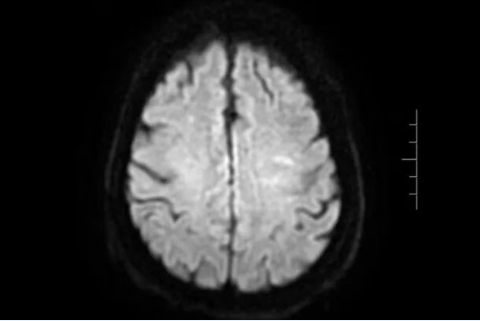

58岁于先生自觉说话不清,左上肢麻木2.5小时,来到青岛西海岸新区中医医院急诊就诊,查体显示言语不利及左侧中枢性面舌瘫。原来他长期高血压却未服药监测,急诊测血压200/130左右。颅脑CT排除出血、排除溶栓禁忌及对症处理后予以静脉溶栓治疗,及时给予完善磁共振示右侧额顶叶皮层新发脑梗死,右侧颈内动脉纤细,考虑大动脉粥样硬化引起的低灌注脑梗死可能。

70岁的牟大叔左侧肢体麻木无力2.5小时就诊,虽有高血压但规律服药,查体示左侧中枢性面舌瘫,左侧肌力5-级,左上肢针刺觉减退。CT显示陈旧性脑梗死软化灶,颅脑CT排除出血、排除溶栓禁忌后予以静脉溶栓治疗,溶栓后无力麻木症状基本缓解。完善磁共振后发现右侧豆纹动脉供血区新发脑梗死。

62岁薛阿姨薛阿姨反复出现右侧肢体麻木无力,持续不缓解后就医。颅脑CT排除出血、排除溶栓禁忌后予以静脉溶栓治疗,溶栓后无力麻木症状较前缓解。完善磁共振后发现基底节区脑梗死,考虑动脉粥样硬化血栓形成。